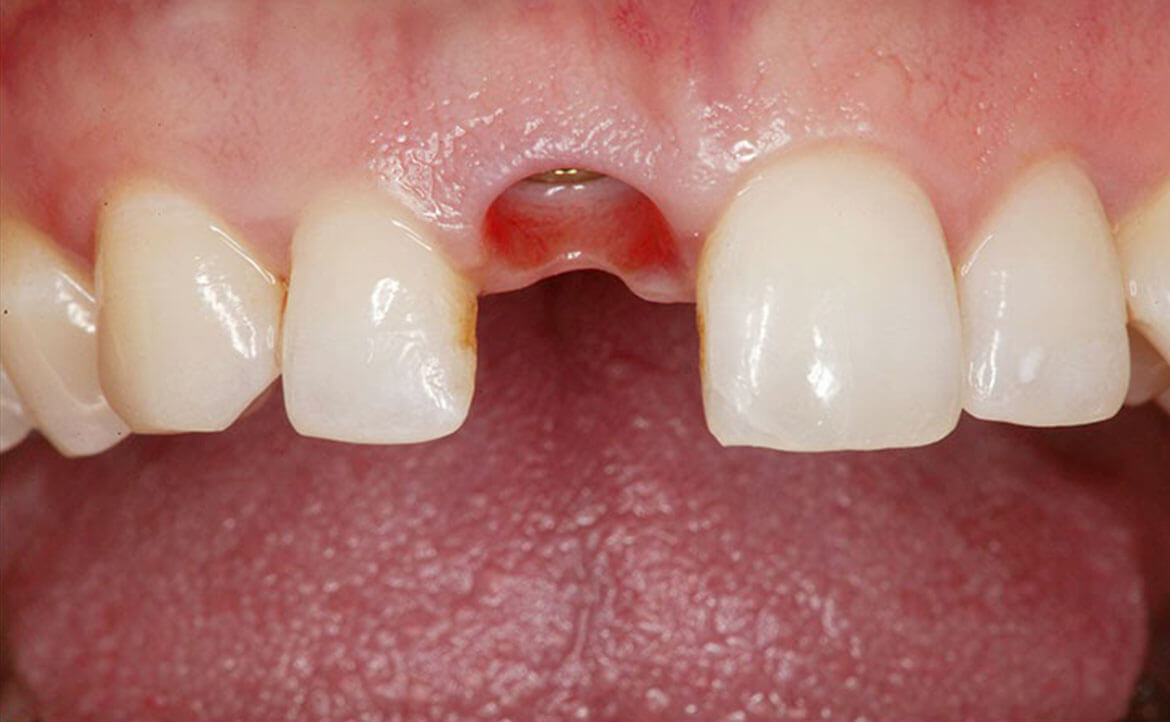

Oltre al ripristino estetico della dentatura, il ponte dentale previene le complicazioni che possono derivare dalla mancanza di un dente. Una volta applicato, completerà il normale processo di masticazione e migliorerà la funzione fonetica.